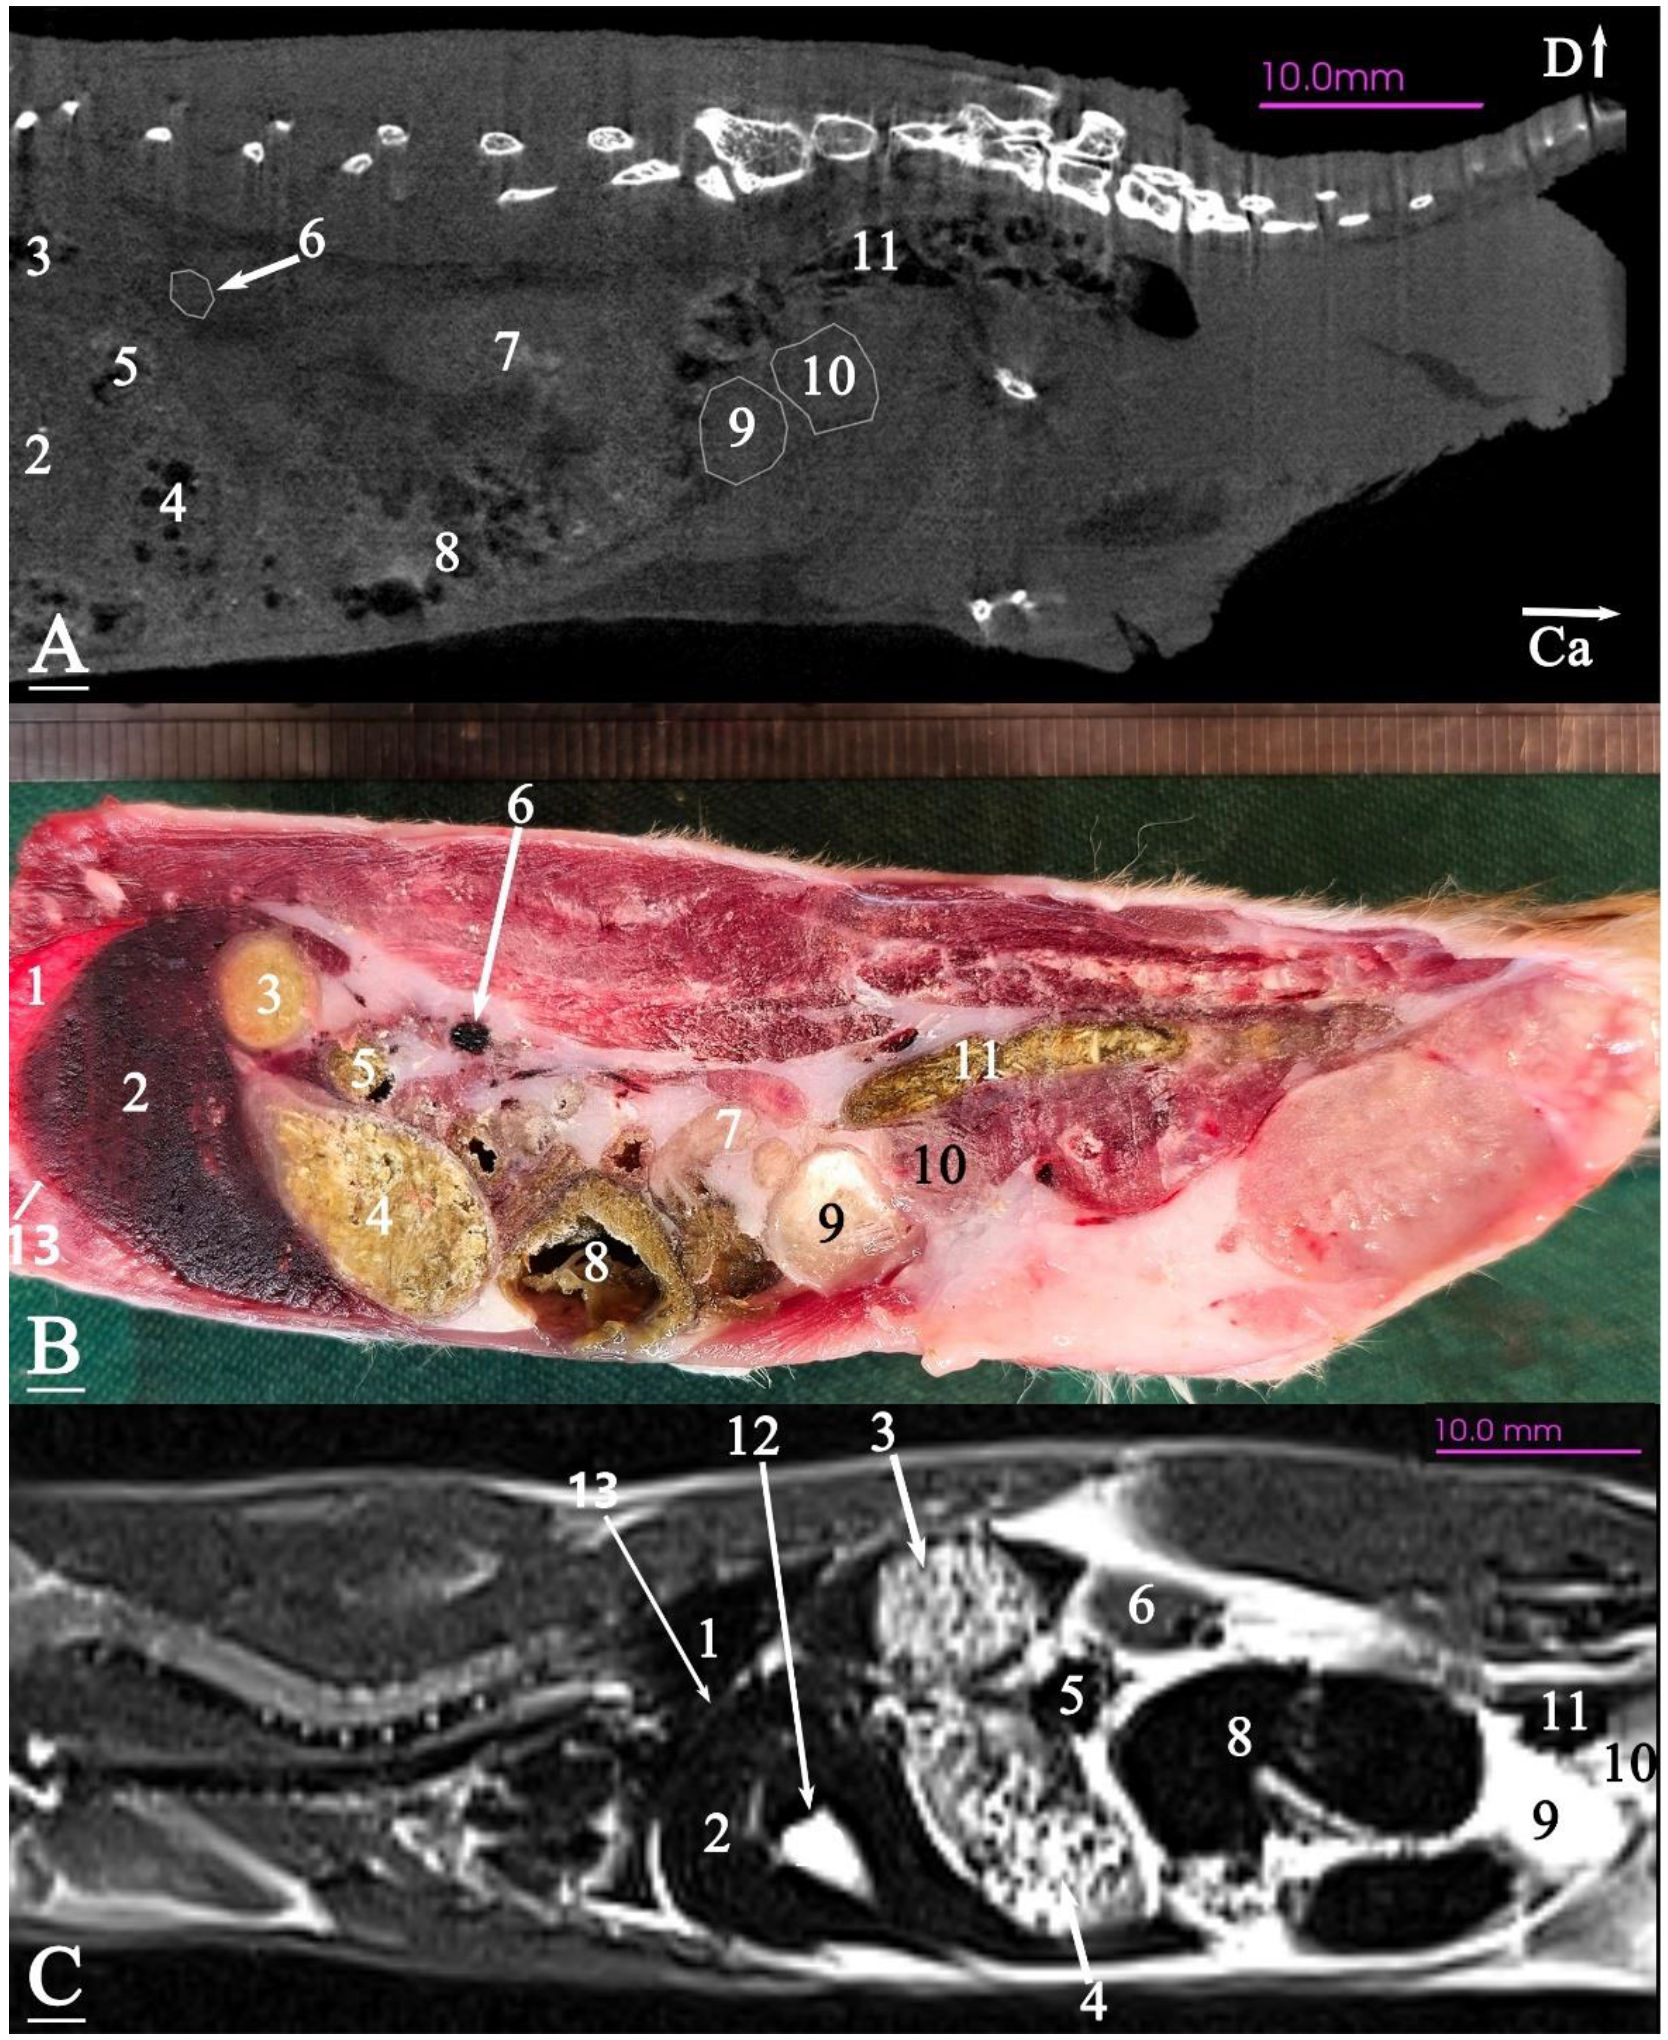

3.2.2. Dorsal Cadaver Slice

3.2.3. Sagittal Cadaver Slice

3.3. Micro-CT Slices

3.4. MRI Slices